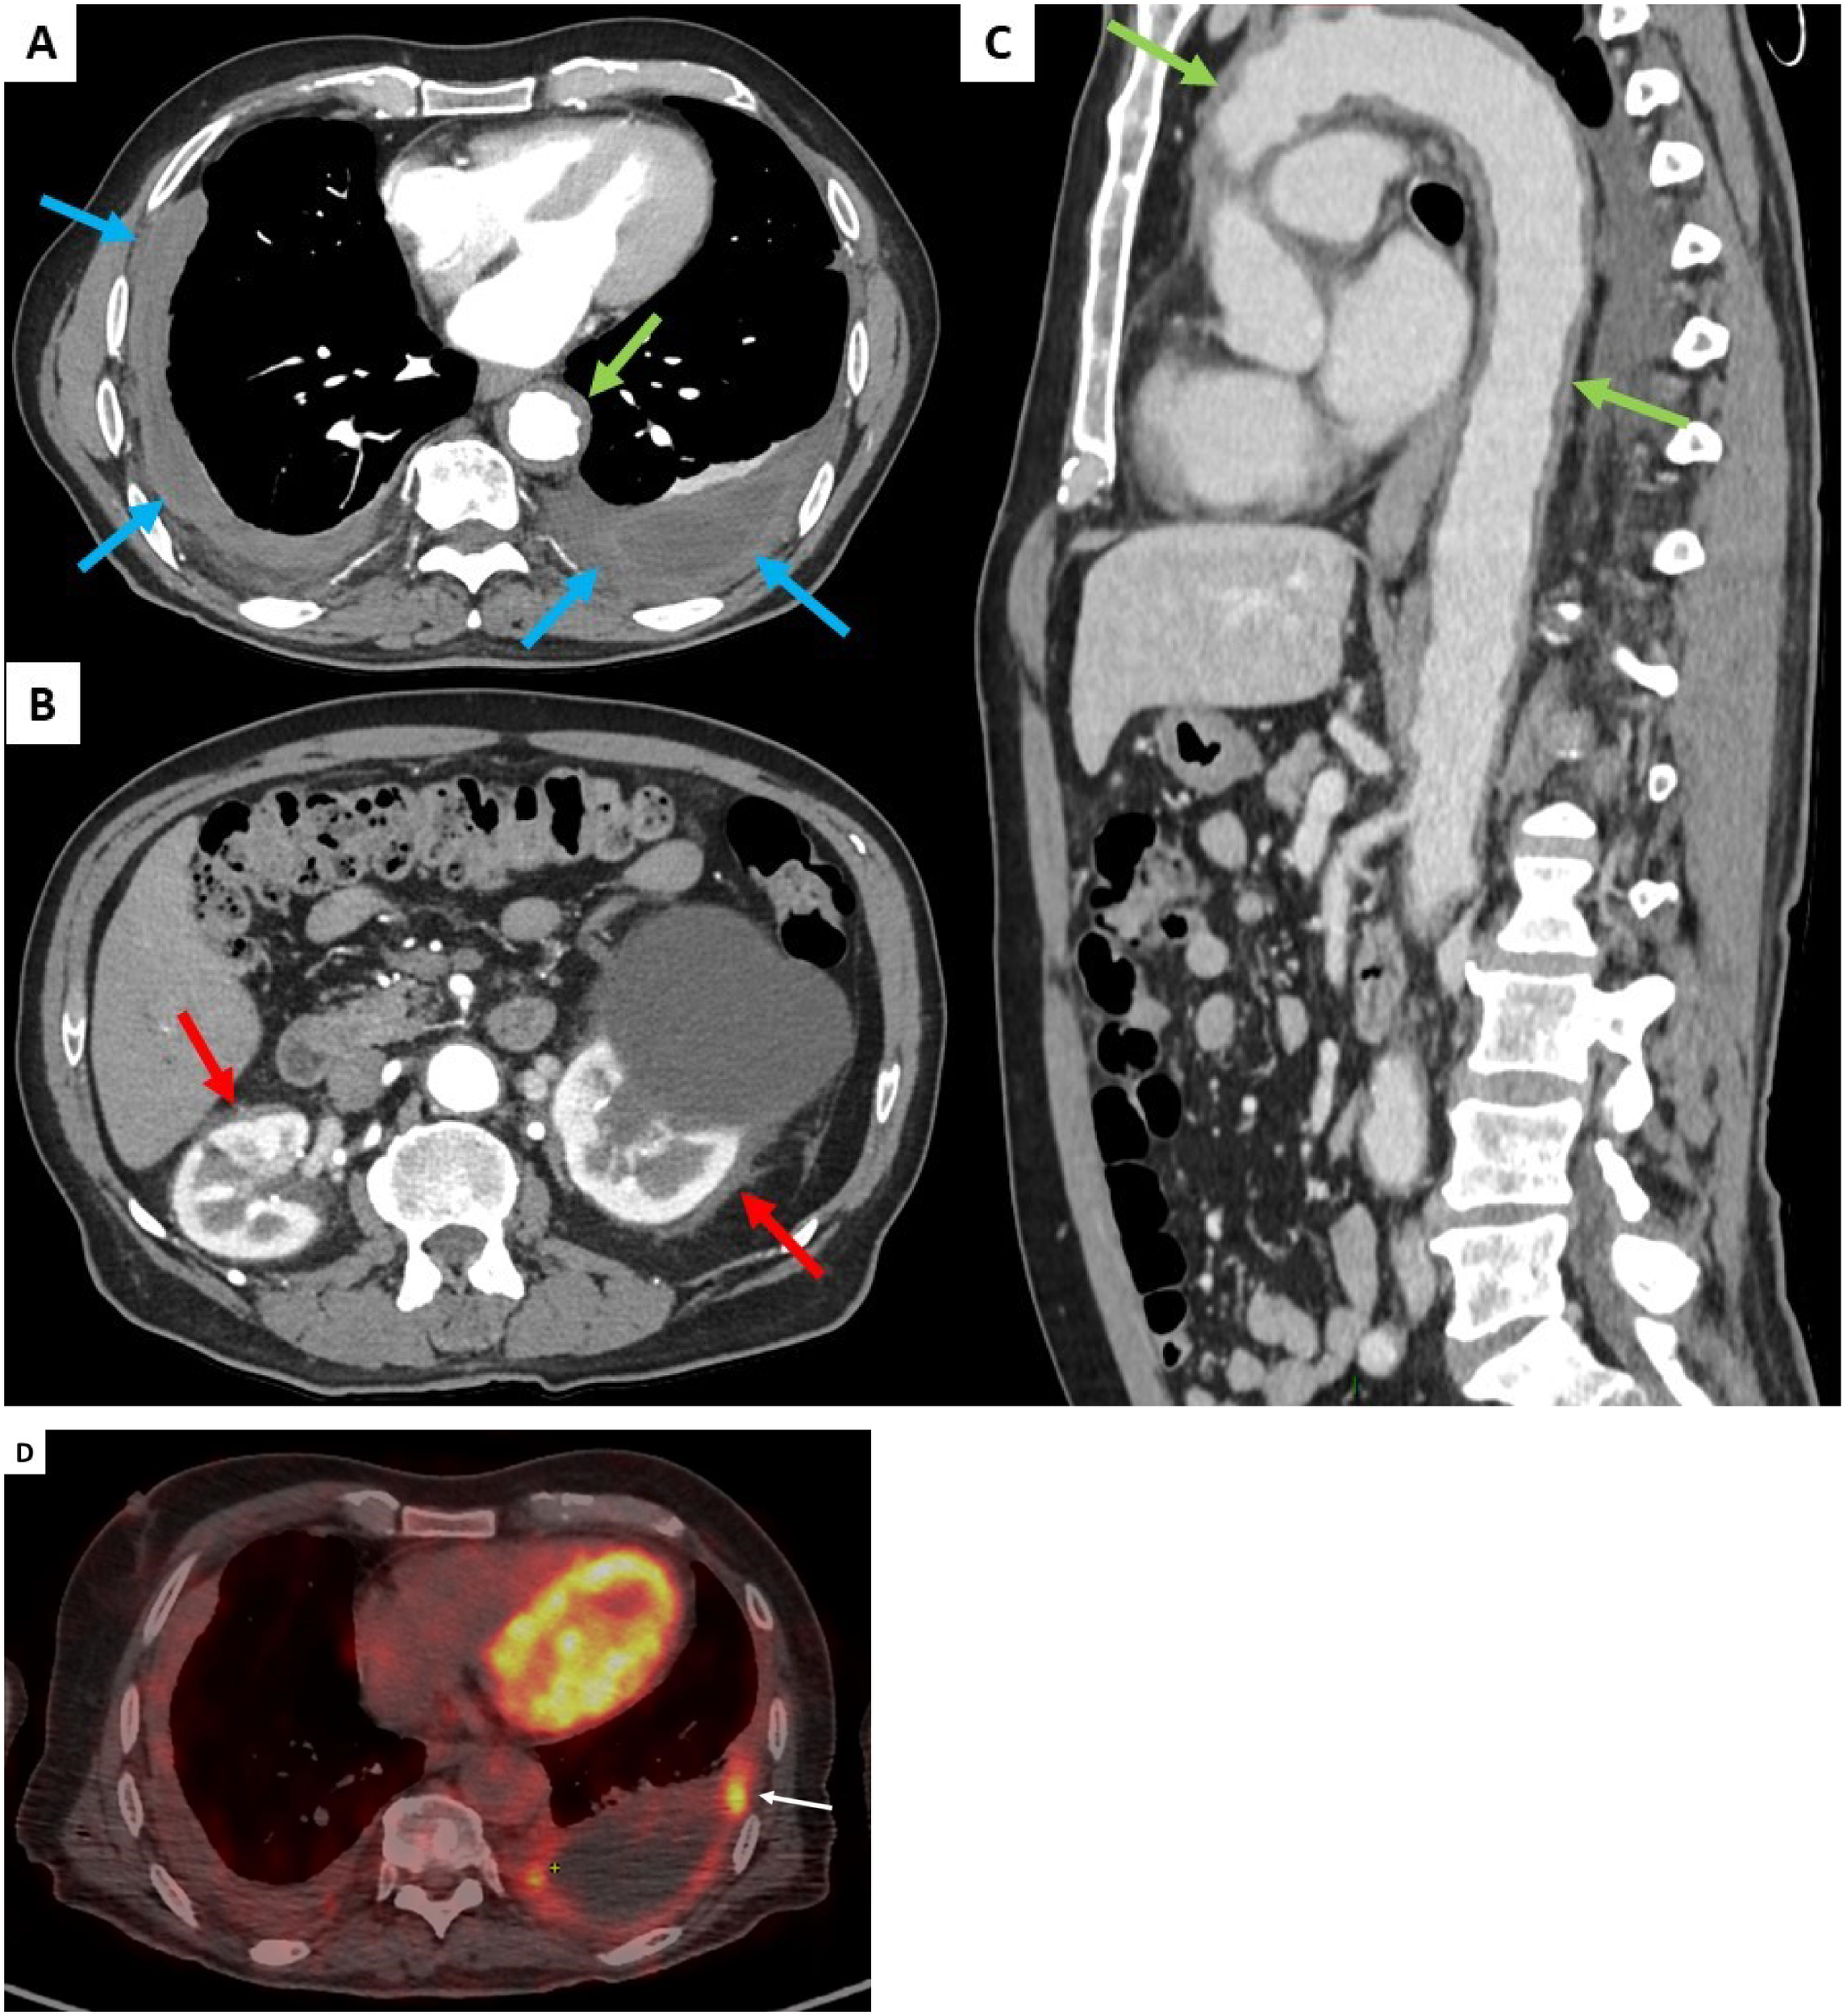

On admission, physical examination showed normal results including cardiovascular and chest auscultation. He denied weight loss, chest pain, and dyspnoea. Laboratory results showed normal C-reactive protein (4 mg/L), negative IGRA test (Quantiferon®), normal IgG4 serum levels, negative ANCA, and negative syphilis serology. Brain gadolinium-enhanced magnetic resonance imaging (MRI) revealed ischemic lacunar sequalae of the left corona radiata and left superior cortex, without intracranial periarterial infiltration. Chest and abdominal computed tomography (CT) scan results showed bilateral pleural thickening (Figure 1A), symmetrical irregular perirenal infiltration (Figure 1B), and periaortic sheathing of the thoracic and abdominal aorta (Figure 1C). An F - 18 fluorodesoxyglucose (FDG)-positron emission tomography (PET) results showed strong FDG uptake found along the left pleura (left pleura SUVmax = maximum standardized uptake value = 6.2), moderate uptake in thoracic and abdominal aortas (arch of aorta SUVmax = 3.9 and abdominal aorta SUVmax = 2.9), and no bone hypermetabolism (Figure 1D).

Figure 1

Contrast-enhanced thoracic and abdominal CT-scan transverse sections (blue arrows, A), symmetrical irregular soft-tissue infiltration in the perirenal spaces (red arrows, B), and thickening of the aorta (green arrows, C). FDG uptake was found along the left pleura (white arrow, D).

Up to 50% of patients show lung and pleural involvement on the CT scan (5). Lung findings in ECD include reticular infiltrative opacities, peribronchovascular infiltrate, focal or diffuse smooth interlobular septal thickening, multifocal micronodules, and ground-glass opacities (8). Honeycombing is rare (<10%) (9). Pleural ECD thickening can be focal or diffuse, and unilateral or bilateral (Figure 1A) (5). No specific pattern or topography characterizes infiltrative lung disease of ECD. The presence of lung lesions and pleural thickening in combination with other systemic findings suggests the diagnosis.

The most common extraosseous site affected in ECD is retroperitoneum including the kidneys, involved in approximately 68% of cases, remaining asymptomatic, or revealed by abdominal pain or dysuria (2, 6, 7). Perirenal infiltration, named the “hairy kidney sign,” may cause large bilateral soft tissue masses and compression effect on kidney (Figure 1B) (7). Retroperitoneal fibrosis is the major differential diagnosis.

Vascular involvement affects mainly the aorta with adventitial histiocytic infiltration and periarterial fibrosis, observed in 56%–85% of patients (2, 6, 7). Diffuse and circumferential infiltration of aorta is characterized by “coated aorta” appearance, observed in 23%–30% of patients (Figure 1C). In our case with initial ischemic stroke, differential diagnosis could also be made with large vessel vasculitis (giant cell arteritis, GCA) where inflammation on the aorta potentially led to FDG uptake. Unlike GCA, aortic infiltration could not resolve during follow-up and may be associated with fibrotic or atherosclerotic lesions for which ECD treatments have no substantial effects (10).